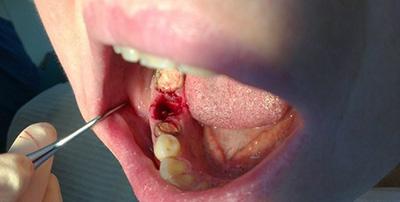

- Во время процедуры был выполнен надрез: чаще всего врач прибегает к такой мере, когда нет коронки зуба или есть неровные корни.

- Повреждение мягких тканей ротовой полости. Обычно возникает при неудобном положении. Лечение заключается в длительном и сложном периоде с применением множества хирургических инструментов. Часто требуется наложения швов на поврежденные слизистые.